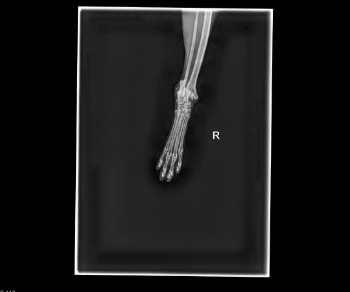

Unser geliebter Kater Maxi wurde angefahren und muss dringend operiert werden. Er erlitt einen schweren Beinbruch und leidet.

Unser wundervoller Kater braucht dringend eine Operation. Sein Beinchen muss operiert/evtl. amputiert werden. Bitte hilft uns mit das durchzustehen.